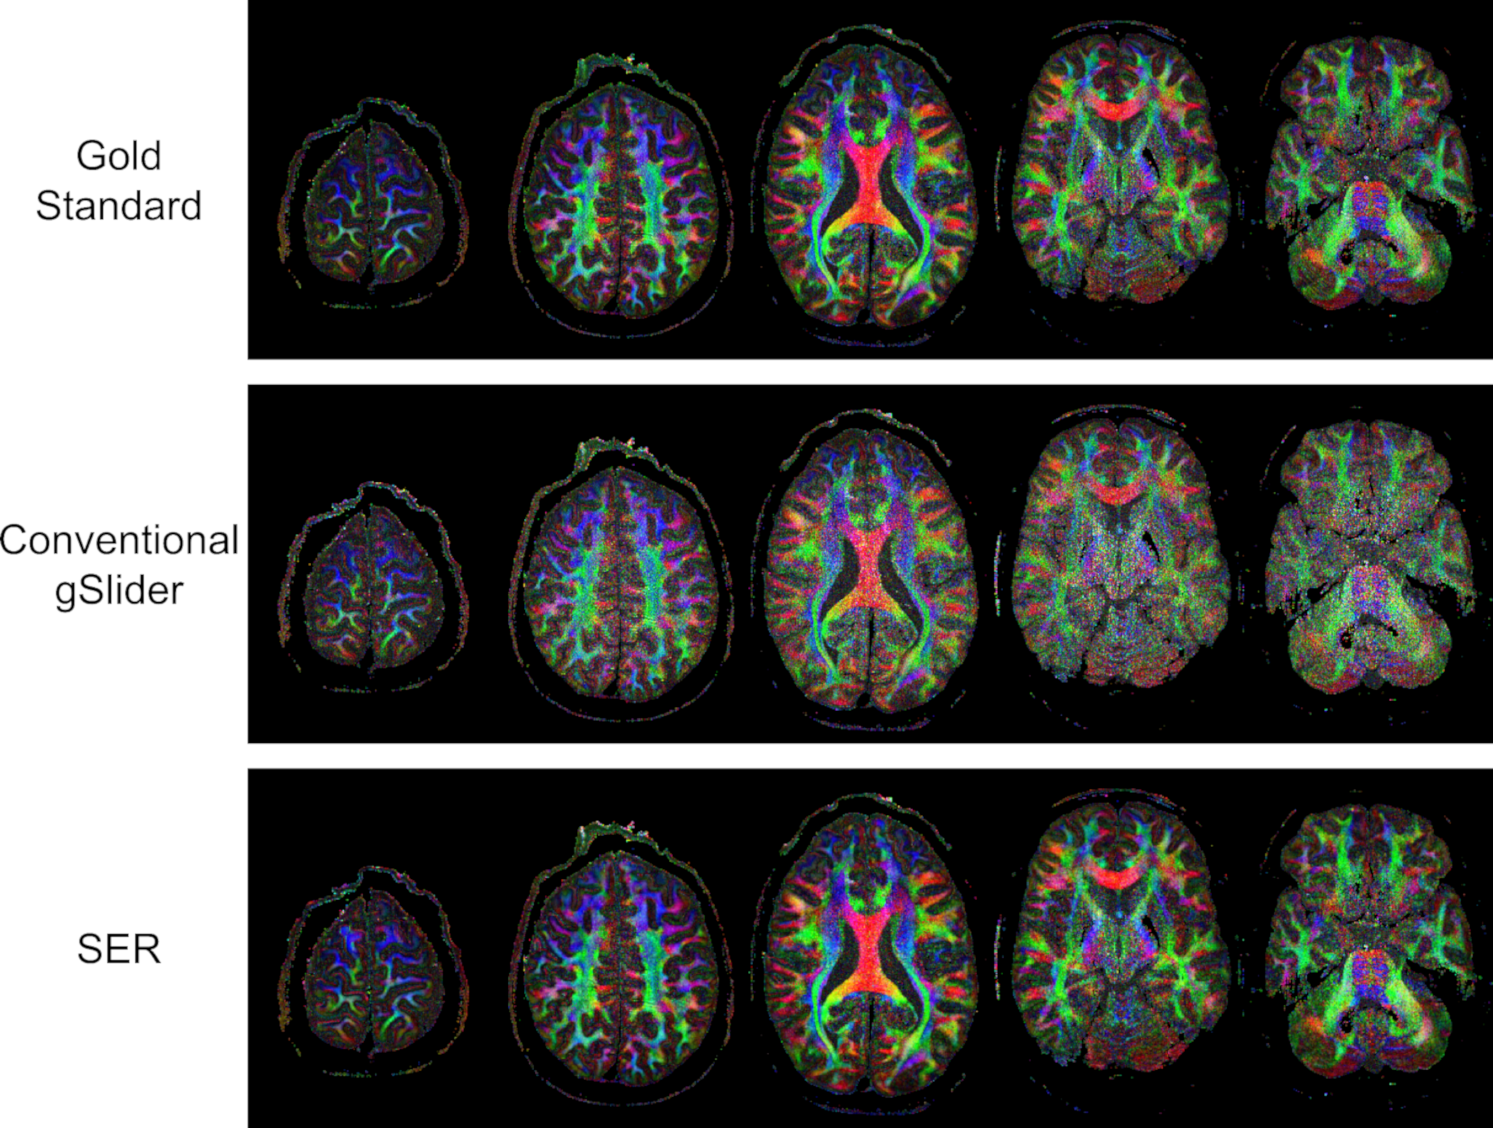

FiguresΒ 4 and 5 respectively show color-coded FA maps corresponding to the same images from Figs.Β 2 and 3, and NRMSE values corresponding to the quantitative DTI parameters (MD and FA) are also shown in TableΒ 1. Interestingly, SER and MPPCA are now the two best denoising methods with respect to these DTI parameters, and SER has a substantial advantage over MPPCA. Visually, Fig.Β 5 shows that SER results in a color FA map that does not appear to be as noisy as the color FA maps from the other methods.

Figure 4: Color FA maps computed based on gold standard, conventional gSlider, and SER images from five slices of the brain volume.

Refer to caption